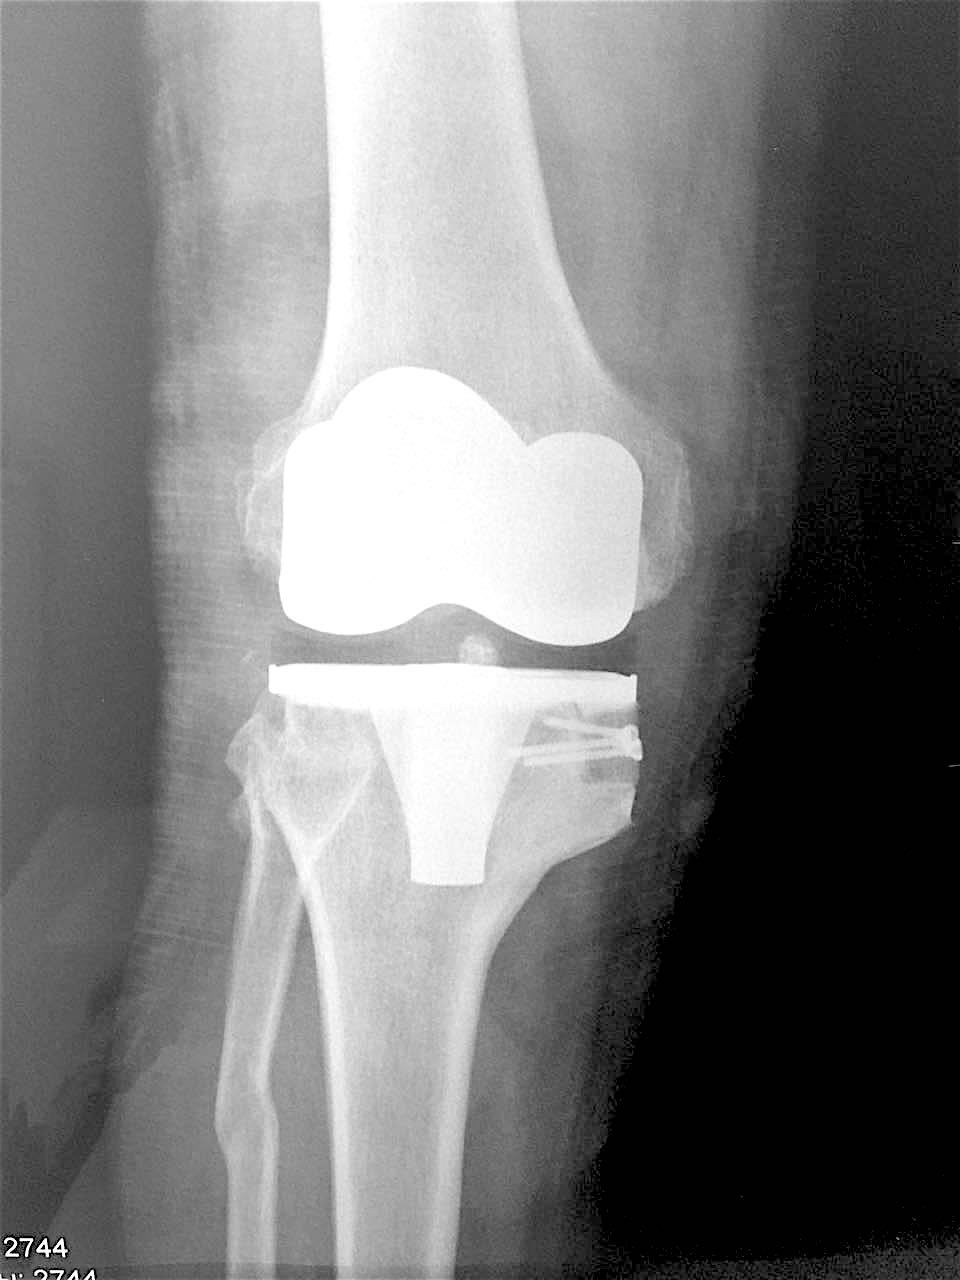

Сделано тотальное эндопротезирование коленного сустава, костная аллопластика материалом «Лиопласт».